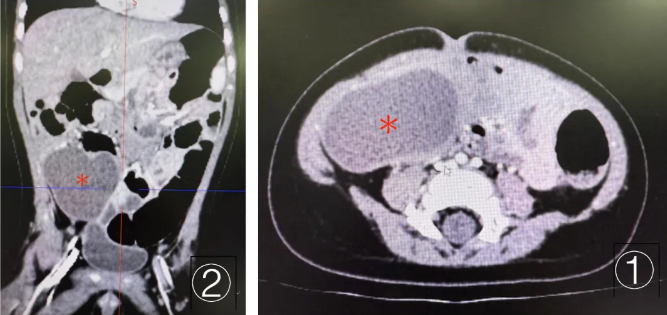

浩浩的术前CT(①为冠状位②为横断面),“*”即指示腹腔囊性占位

看着日渐消瘦、精神萎靡的浩浩,家长心急如焚,四处求医后辗转找到了首都医科大学附属首都儿童医学中心新生儿外科。接诊后,医生第一时间为孩子安排了腹部增强CT检查,结果显示其腹腔内有一个体积较大的囊性占位,周边肠腔伴有扩张、积液。结合临床经验判断,浩浩已经出现明确的不完全性肠梗阻,必须尽快手术干预。术中确诊为肠重复畸形,这个囊肿就长在回盲部,像一块坚硬的石头紧紧压在肠管上,直接导致肠腔狭窄。医生凭借精细操作,成功将囊肿完整剥离,同时保住了孩子的回盲瓣和肠管完整性,最大程度保护了肠道功能。术后浩浩恢复状况十分理想,很快就能正常大口吃奶了。